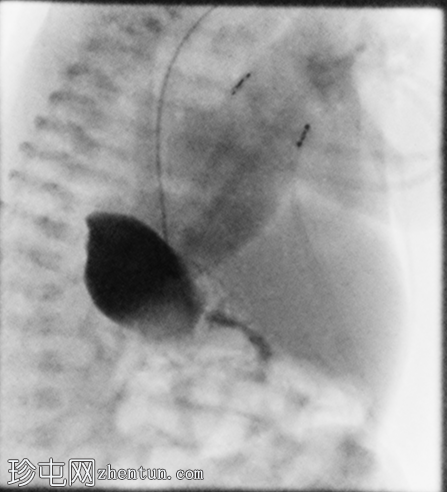

正位

6.png

侧位

7.png

定位片显示肠道气体分布无梗阻,经食管插管终止于右上腹。

胃位于右上腹。观察到轻度中段食管反流。造影剂在近端十二指肠的延迟通过量极少,这属于异常情况。

延迟正位和侧位X线片显示肠内容物通过时间极短。